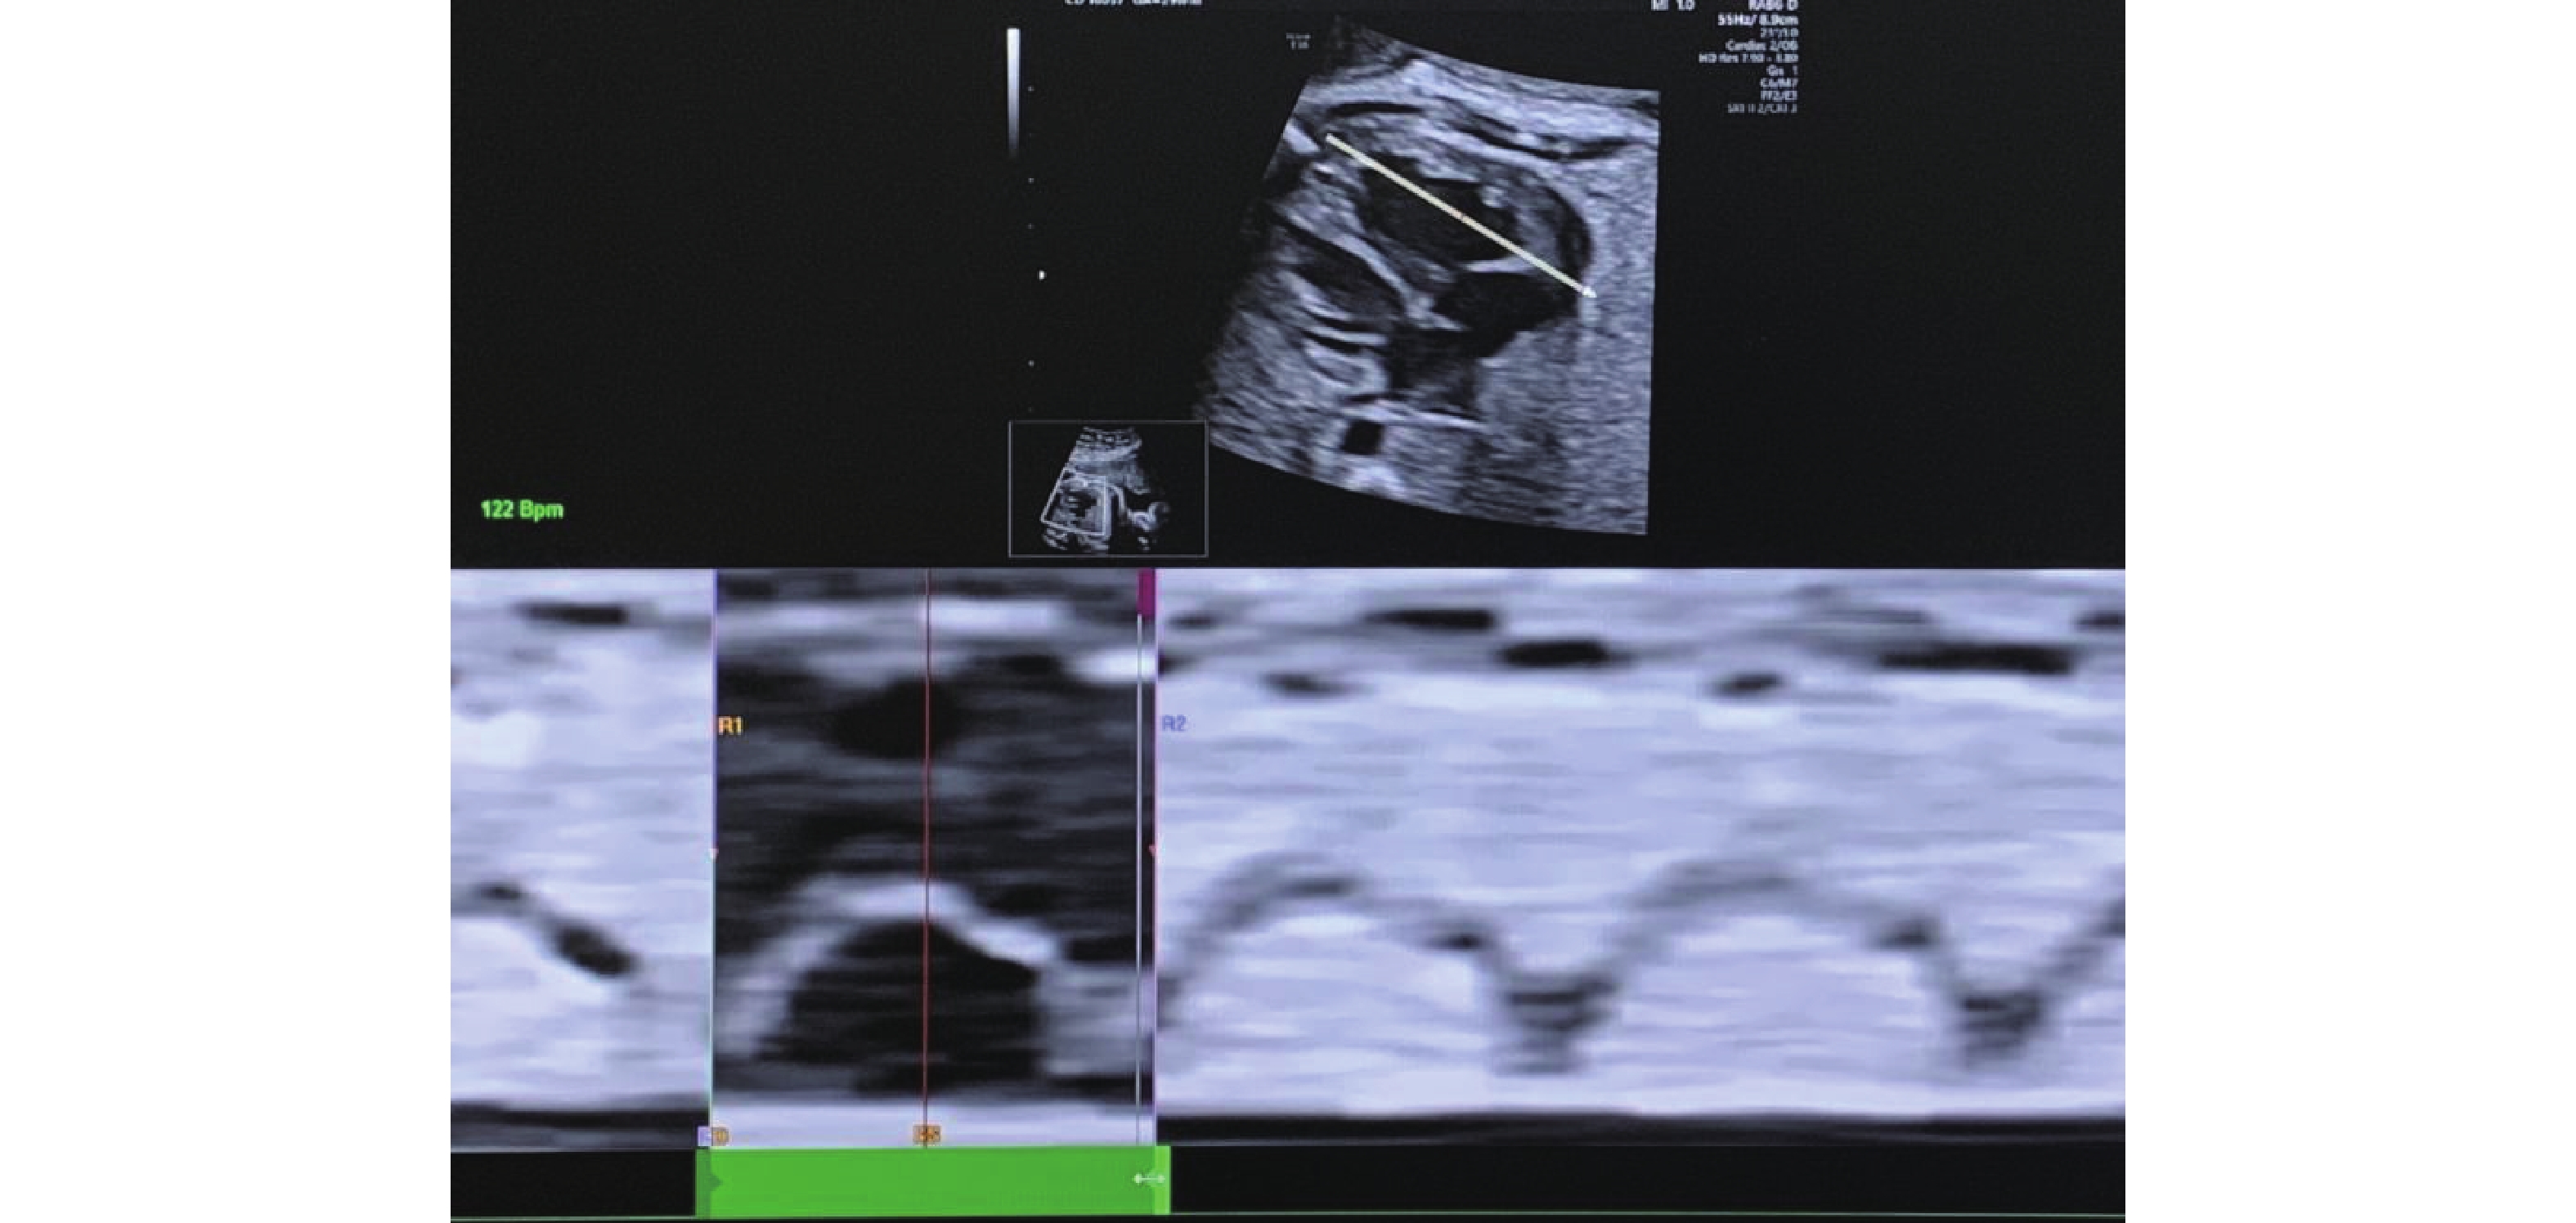

Figure 3

Determination of the cardiac cycle. This figure shows the determination of the right ventricular cardiac cycle to get the annular movement in M-mode by drawing a line perpendicular to the annulus of the right ventricular chamber in the four-chamber view. The cardiac cycle from end-diastole to end-diastole between two troughs is marked on the M-mode graph along with the end-systole. (Images were acquired on E10 Voluson ultrasound machine and analysed using FetalHQ software)"